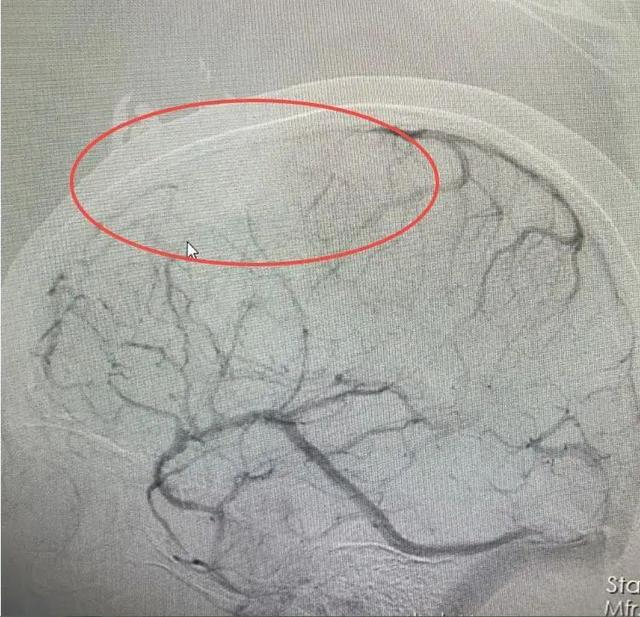

医院接诊医生仔细分析后,发现婷婷颅内病变不是脑肿瘤。结合病史和相关影像资料,该院神经内一科副主任匡祖颖初步怀疑是颅内静脉窦血栓,进一步完善全脑血管造影,证实是颅内静脉窦血栓形成合并出血